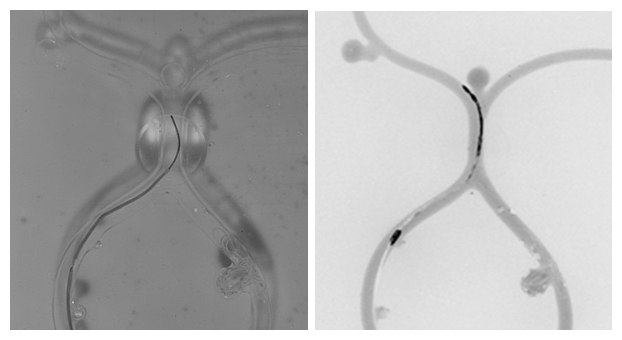

血管モデルの可視光による画像(左)と非被爆血管内治療シミュレータによるX線模擬画像

開発したシステムで血管模擬モデルの撮影の結果を図2に示します。まず、血流モデルに造影剤を流し入れることにより、血管の走行を撮影したところ(図2A)、血管モデルに設置した分岐や動脈瘤が認められました。図2Bは造影剤が流れた後、ガイドワイヤーとカテーテルを挿入した状態を示しています。ここからガイドワイヤーとカテーテルに設置した蛍光色素の配置を区別して観察できます。実際のガイドワイヤーとカテーテルの先端には、鉛などでX線の通りにくい箇所を作り、X線で区別できるよう透過特性を変えており、同様の表示ができています。図2Cは、造影剤とガイドワイヤー、カテーテルを重畳表示した画像です。血管の走行と合わせて、ガイドワイヤーの方向と挿入を操作することにより、任意の分岐を進むことができます。

最後に、開発したシステムと一般のカメラでの撮影の比較を行いました。図2Dでは、血管モデルの走行とガイドワイヤーとカテーテルが一緒に写っており、血管モデルの形状や上下の位置を陰で判断できるなど、X線透視下での血管内治療と大きな違いがあり、トレーニングの成果が期待できません。